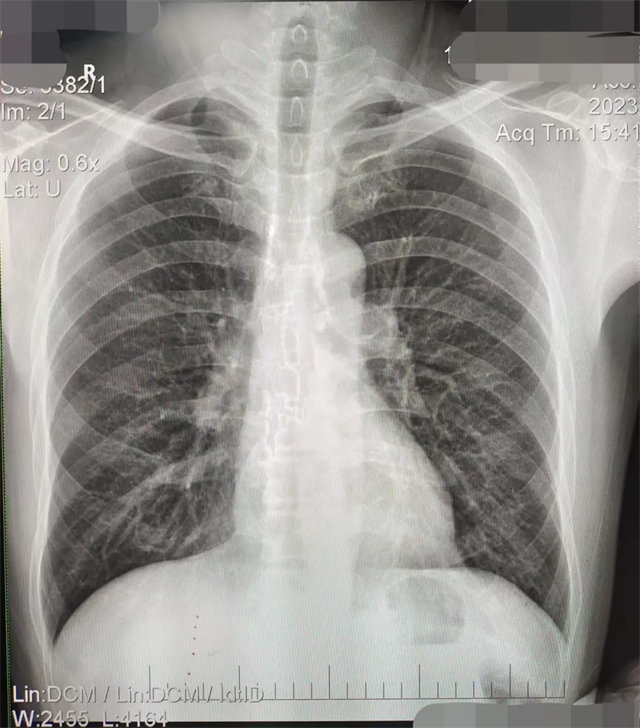

缺陷:肩胛骨未完全拉離肺野,吸氣不完全,存在金屬偽影遮擋,略有聳肩,且肺尖顯示不好,圖像顆粒感較強,管電流量不夠,信噪比偏低。

解決:去除金屬物品后,按標準體位,使患者雙肩旋前與前胸一并緊貼成像件,適當(dāng)調(diào)高mAs,然后深吸氣后屏氣曝光。